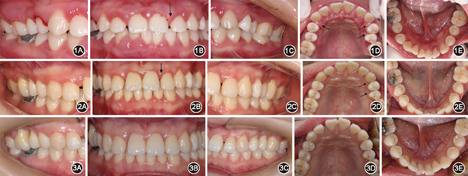

治疗前及治疗后随访结果见图1,图2,图3,图4,图5,图6,图7,图8。

像;B:正面

像,箭头示牙间隙;C:左侧

像;D:上颌

面像,箭头示牙间隙;E:下颌

面像

像,箭头所示21和22牙间隙关闭;C:左侧

面像,箭头所示25自发回位及23和24牙间隙关闭;E:下颌

像;C:左侧

面像;E:下颌

口外检查可见面部不对称和张口偏斜。口内检查可见牙龈红肿,前牙区和后牙区均存在牙齿移位和明显的牙间隙(图1)。牙周检查结果见图4A,探诊出血阳性位点达100%,探诊深度超过4 mm的位点达65%,松动牙占全口牙85%,其中Ⅲ度松动的牙齿数量达50%。影像学检查结果显示除外个别牙,余牙的牙槽骨吸收均达根长的1/3至根尖,同时发现存在右侧上颌窦炎(图5A)。应用K7咬合评估分析系统(K7 evaluation system,Myotronics-Noromed Inc,美国)检测发现患者双侧咀嚼肌电位严重不对称,下颌运动向左偏斜达17.3 mm(图6)。咬合力评估分析系统(T-scan system,Tekscan Inc,美国)显示存在早接触和

3年后随访显示,牙龈轻度红肿,病理性移位的25自动排齐,21和22以及23和24间缝隙关闭(图2)。探诊深度超过4 mm的位点百分比降至14%,Ⅲ度松动的牙齿仅占11%。影像学检查结果示牙槽骨骨量和密度均有增加,可见26、27、36近中和15、16的骨量明显增加;右侧上颌窦的炎症也得到控制(图5B)。图8示CT影像是在同一断层获取,15、16的放大影像清楚可见明显的骨量增加。8年后随访结果显示,病理性移位的牙齿未复发(图3),牙龈炎症控制良好,牙松动情况持续减轻。从2011年初始治疗至2019年,8年多来患者的牙周及整体情况显著好转;复查结果显示牙龈无明显红肿,回位牙齿维持稳定并未复发。无探诊深度超过4 mm的位点,Ⅱ度及以下松动牙齿仅占8%,无Ⅲ度松动牙齿(图4B),除15、16牙龈明显退缩,涉及退缩的还有36和24、25、26、27。影像学检查结果显示牙槽骨骨量和骨密度均进一步增加,骨白线逐渐清晰(图5C,图8)。患者对治疗结果非常满意。